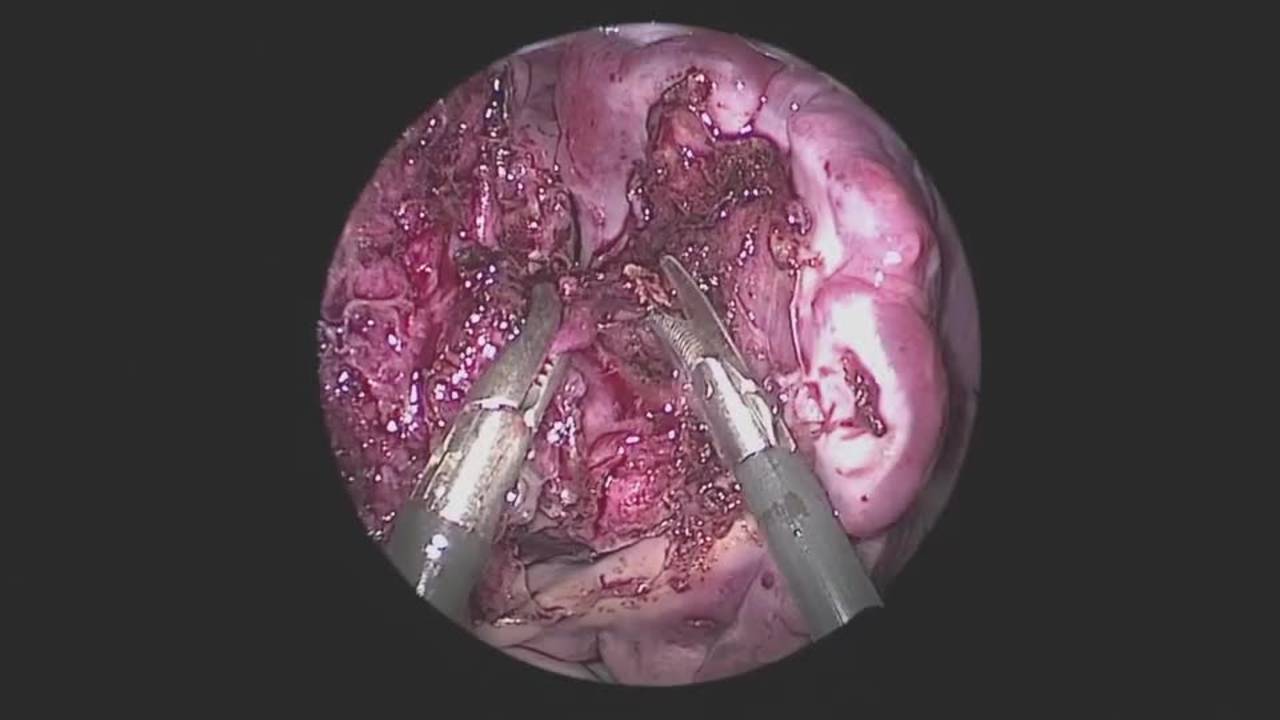

Thoracoscopic Left Lower Lobectomy for Sequestration